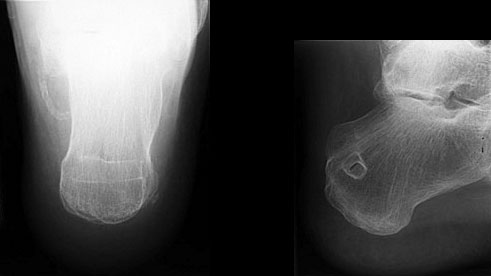

Knöcherne Ausrisse lassen sich in der seitlichen Röntgenaufnahme des Sprunggelenkes ausschließen oder beweisen (Abb. 5). Eine Sonderform bilden hier die Entenschnabelfrakturen des Kalkaneus.

Abbildung 5

Der geübte Untersucher kann anhand des seitlichen Röntgenbildes die Diagnose einer Achillessehnenruptur stellen. Die Konturen des Kager-Dreiecks – gebildet von der ventralen Begrenzung der Achillessehne, der posterioren Tibiakante und der kranialen Kalkaneuskortikalis – verstreichen im Rupturfall (Kager 1939). Die MRT- Diagnostik spielt für die Primärdiagnostik der frischen Achillessehnenruptur eine untergeordnete Rolle und ist im Normalfall nicht notwendig. Anders verhält es sich bei den chronischen Rupturen. Hier ist die MRT ein wichtiges Diagnostikum insbesondere in Hinblick auf die Beurteilung der Sehnen- und Muskeldegeneration (Abb. 6).